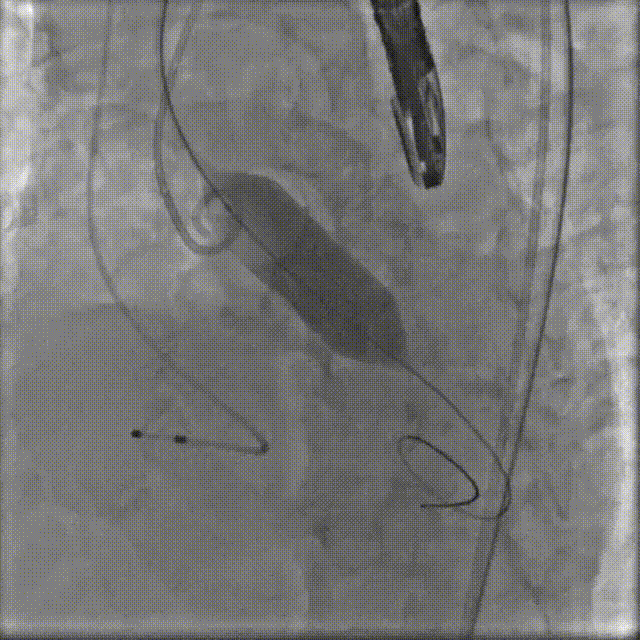

TaurusElite AV26瓣膜轻松过弓跨瓣,瓣膜初始定位瓣环0位,120bpm起搏下精准释放,释放到工作位后造影显示锚定充足,位置良好,冠脉未见遮挡,继续完成释放。

瓣膜初始定位

瓣膜释放过程

瓣膜释放后造影观察,根据影像判断反流较多,选择23mm球囊进行后扩。球囊后扩后反流量减少,瓣膜形态佳。

瓣膜脱钩

工球囊后扩